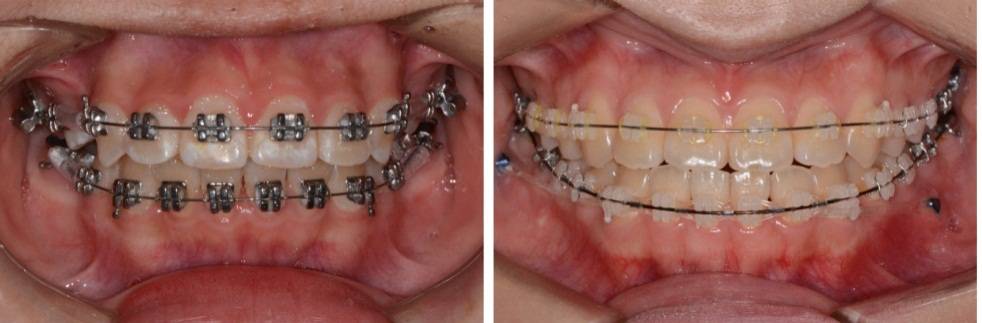

照相:包括口外像和口内像。这些照片不仅是医生诊断和制定矫治方案的重要依据,同时也是治疗前后进行对比的重要资料。

口外照像(上)和口内照像(下)